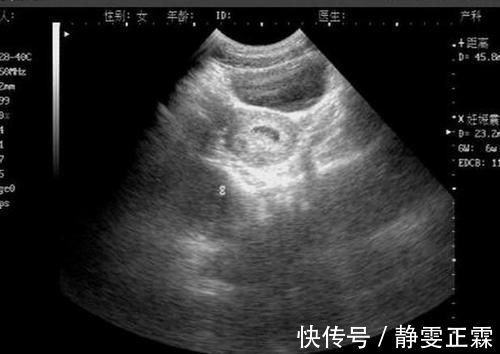

文章插图